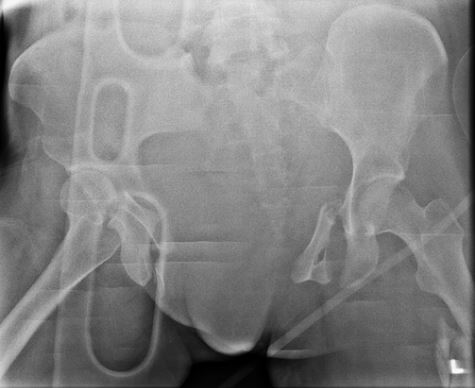

A 24-year-old male sustains the injury seen in Figure A after being thrown from a motorcycle at a high speed. Which of the following fixation methods has been shown to be the most stable fixation construct for this injury?

This is an APC III injury, which is rotationally and vertically unstable with damage to the anterior ring, pelvic floor and posterior ligamentous complex

Sagi showed that optimal treatment is percutaneous iliosacral screw and anterior ring ORIF